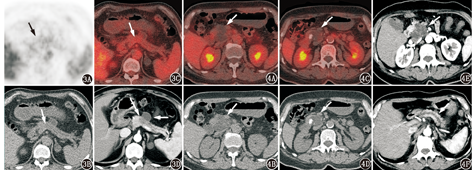

胰头病变为囊实性,常见的肿瘤性病变包括胰腺导管腺癌、胰腺神经内分泌肿瘤、胰腺导管内乳头状黏液性肿瘤(intraductal papillary mucinous neoplasm, IPMN)、胰腺实性假乳头状瘤、胰腺浆液性囊腺瘤(囊腺癌)、胰腺黏液性囊腺瘤(囊腺癌)等,非肿瘤性病变主要为胰腺炎。虽然本例胰头病变FDG代谢未见明显增高,但恶性肿瘤中胰腺导管腺癌、胰腺低级别神经内分泌肿瘤、IPMN都有可能表现为完全正常的FDG代谢活性(图3,图4),因此FDG代谢不高不能排除胰腺恶性肿瘤的可能性。

3.本例无明显黄疸的临床表现,CT仅见胰管轻度扩张,胆总管扩张不明显,MRI见胰头内胆总管中下段渐进性、向心性变窄(图2F,红箭头示),系沟槽状区域内增生的炎性纤维组织包绕压迫胰头区的胆总管所致,受累的胆总管节段较长,与胰头癌、胆管癌的胆总管突然截断、上游胆管明显扩张的表现有所不同。临床上GP也多无黄疸或黄疸症状较轻,与胰头癌进行性加重的黄疸表现不同。此外,由于沟槽区增生的炎性纤维组织也可累及胰管周围,因此也有远端胰管轻度扩张的表现(图2E,红箭头示),这一点与胰头癌表现较为相似。

4.本例胰头病变周围脂肪间隙密度增高,并可见低密度影包绕肠系膜上动脉(图2A,图2B,图2C,蓝箭头示),病变周围可见多发淋巴结影(图像未显示),GP和胰腺癌中均可出现这种征象,此征象不易鉴别两者。增强CT、MR见到脉管内癌栓为诊断胰腺癌的有利证据,而GP为血管外压性改变,血管内无侵犯。